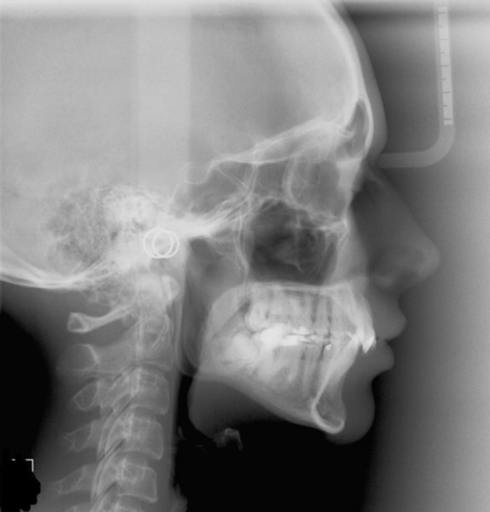

HI! I would like some advise. I went to see 2 different orthodontist and they gave me 2 very different way to treat my condition. I have an overbite and that might be one of the reason that I do snore. Me teeth close correctly together (no problem to eat).When I was very young, a dentist removed my tooth number 33 because of crowding (now all dentists tell me that he shouldn\'t have done that be its done). One of the orthodontist told me that I might not require a jaw surgery and he suggested to start with invisalign and to just move all my teeth straight (not removing any teeth or adding any teeth. He thinks that by moving my teeth straight it might close a bit the gap between my lower and upper teeth. The other orthodontist told me I require a jay surgery. He would put me braces on and then remove my tooth number 44 or 45 (to correct the fact that my tooth number 33 is missing), and then I would have a jaw surgery and continue treatment with braces. The thing is, I really am scared about the surgery. I don\'t really want to do it. But I want to do this right. also, the option of having invisalign is very good. What is your opinion. Thanks